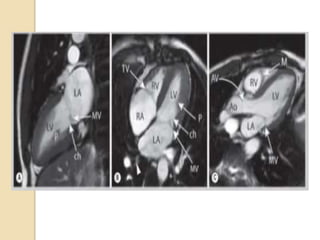

 The twomain planes used for cardiac MRI include the body (scanner) planes and the cardiac planes.  Body Planes Body planes are oriented orthogonal to the long axis of the body and consist of axial, sagittal, and coronal planes .

 The axialplane can depict the four chambers of the heart and the pericardium simultaneously.  The sagittal plane can show the great vessels arising in continuity from the ventricles.  The coronal plane can be used to assess the left ventricular outflow tract, the left atrium, and the pulmonary veins.

Cardiac planes  Thestandard cardiac planes are established using the scout images and include short axis view horizontal long axis (four-chamber view) vertical long axis (two-chamber view)

 These planesare prescribed along a line extending from the cardiac apex to the center of the mitral valve (long axis of the heart) using the axial body plane images.  The short-axis plane extends perpendicular to this true long axis of the heart at the level of the mid left ventricle.  The horizontal long(4 chamber) axis is generated by selecting the horizontal plane that is perpendicular to the short axis  The vertical long (2 chamber)axis is prescribed along a vertical plane orthogonal to the short-axis plane